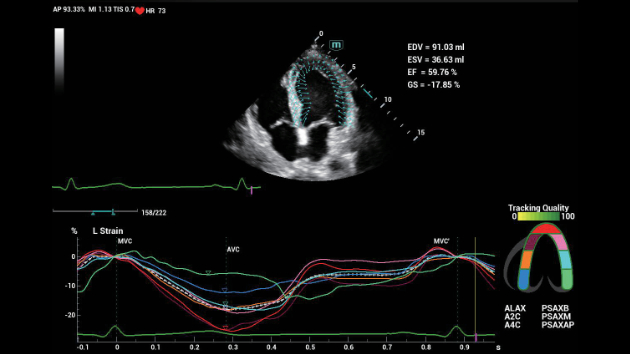

De Consona biedt nieuwe en concrete oplossingen die effici?nt helpen bij het stellen van een vlotte diagnose voor veel verschillende soorten pati?nten.

Ongeacht of u werkzaam bent in een ziekenhuis of kliniek, of uw vaardigheden aanscherpt op het gebied van algemene beeldvormingstoepassingen, vrouwengeneeskunde of cardiovasculaire specialismen, in deze serie vindt u zeer krachtige hulpmiddelen waarmee u aan kop kunt blijven.

Uitgebreide?oplossingen voor beeldvorming aangestuurd door ZST?+

Het ZST+?platform is een buitengewone innovatie en revolutie in de wereld van echografie. Het transformeert echografiegegevens van conventionele bundelvorming naar kanaalgegevensverwerking. Het overwint de traditionele afweging tussen ruimtelijke resolutie, temporele resolutie en weefseluniformiteit, en levert een uitzonderlijke beeldkwaliteit voor oneindige beeldvormingsoplossingen met non-stop verbeteringen.